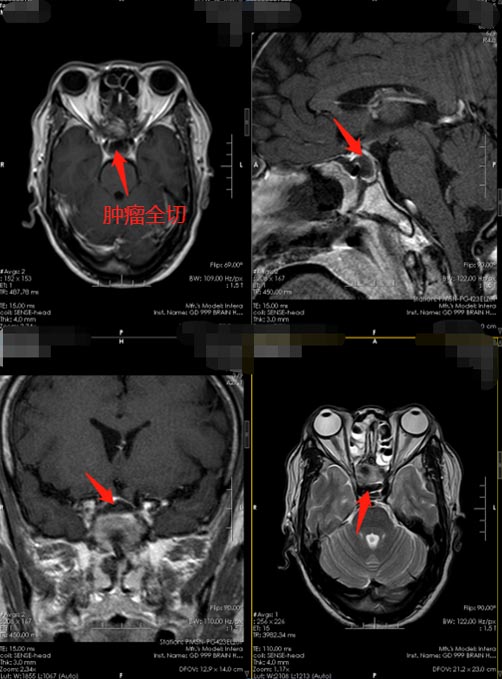

▲术后

术后,方先生的头痛消失,视力下降症状缓解,病理报告:垂体腺瘤。垂体腺瘤一般起病潜隐,早期可无症状,其临床表现主要表现在占位病变的扩张作用及激素的异常分泌,如头痛、视力减退、视野缺损、中枢性尿崩症、激素分泌过多症状或继发性激素缺乏症状等。垂体腺瘤的头疼,通常情况下是因为占位效应导致,或鞍膈刺激造成,一般把占位效应解除之后,绝大多数患者的头痛症状能得到改善。